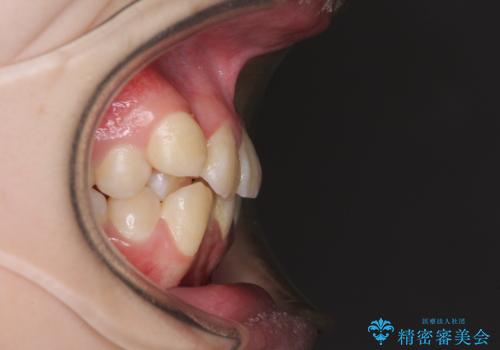

八重歯で正中が右にずれている ワイヤー装置での抜歯矯正で正中位置を改善

- 上下の八重歯と前歯のデコボコを気にして来院された患者様です。

右上の八重歯が特に著しく、上顎正中が右側にシフトしていました。

デコボコが強いため小臼歯4本を抜歯し、上顎正中を左側に移動させるために補助装置を使用して、ワイヤー装置にて矯正治療を行うこととしました。